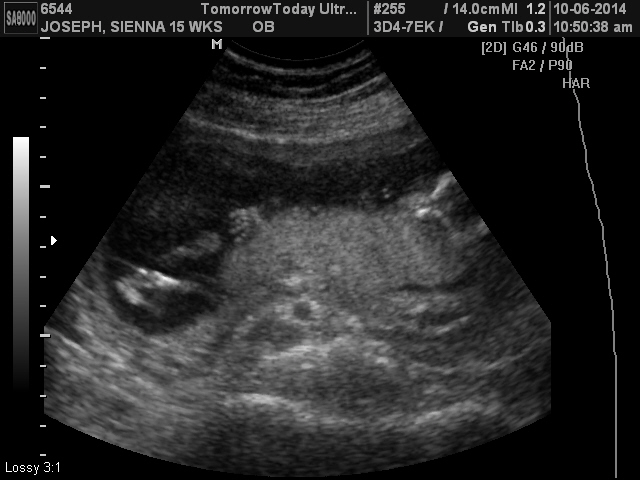

The first picture am I supposed to see the genitalia?